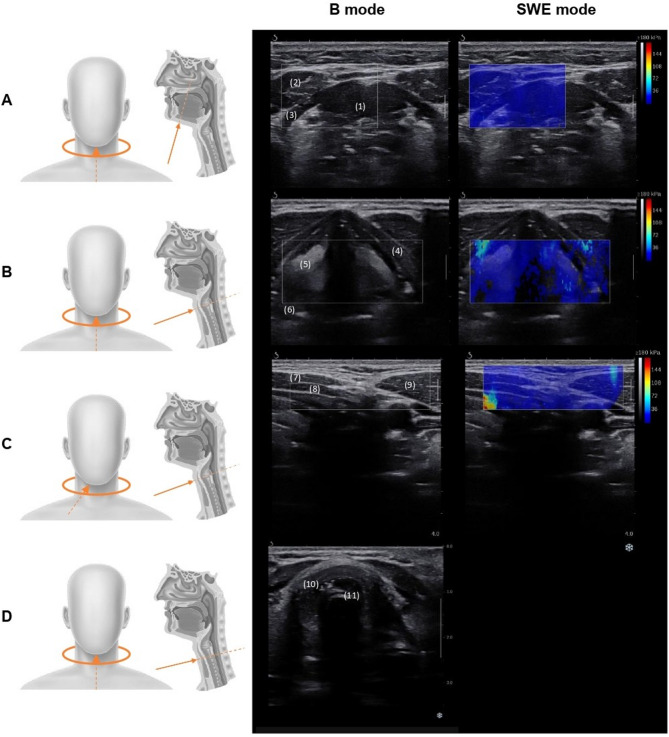

Fig. 1.

Ultrasound imaging plans showing probe position (left) and images obtained for each plan (right). Images of plans A, B and C were acquired in both B and SWE mode, images of plan D in B mode. Plan A: suprahyoid muscles plan – (1) geniohyoid muscle (2), anterior belly of the digastric muscles (3), mylohyoid muscle; Plan B: vocal cords plan – (4) thyroid cartilage (5), vocal folds (6), arytenoid cartilage; Plan C: infra-hyoid muscles lateral plan – (7) sternohyoid muscle (8), sternothyroid muscle (9), sternocleido-occipito-mastoid muscle; Plan D: cricoid cartilage plan – (10) cricoid cartilage (11), intubation tube artefacts